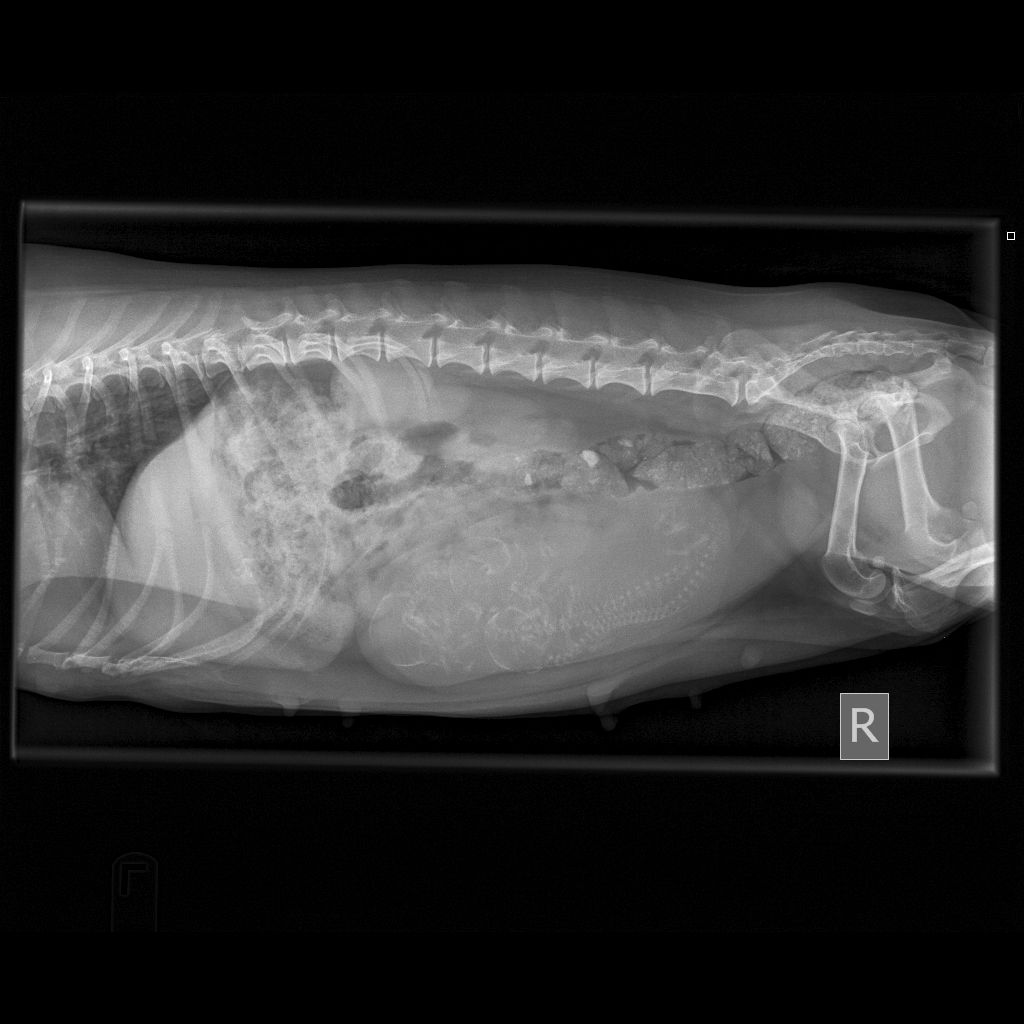

9/14/17 - I had Caper xrayed today and she has 3 puppies. All of them look to be good sized. Fingers crossed for an easy whelping!!